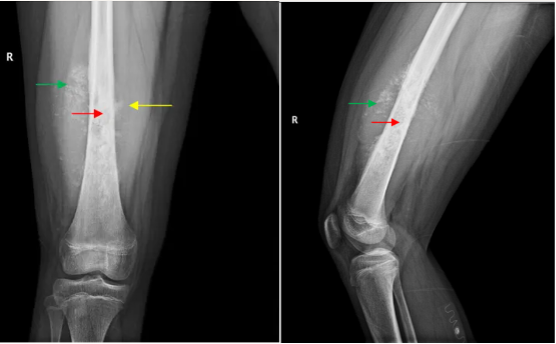

骨样骨瘤是一种孤立性的成骨性肿瘤,为第三大常见的良性骨肿瘤,仅次于内生软骨瘤及非骨化性纤维瘤。好发于5-30岁的儿童与青年(男女比例3:1),通常发生在长骨的骨皮质中。使用CT以及核素骨扫描是骨样骨瘤诊断的主要手段。

软骨母细胞瘤(chondroblastoma)为良性肿瘤,占所有骨肿瘤的比例不到1%,常发生于儿童和青少年,好发于长骨的骨骺:股骨、肱骨和胫骨。组织学上,软骨母细胞瘤由密集排列的软骨母细胞、多少不一的破骨细胞样巨细胞以及钙化的软骨样基质构成,软骨母细胞瘤的瘤细胞核中可见H3.3 K36M阳性表达。治疗上彻底刮除并辅助瘤腔处理是主要治疗手段,由于病变常位于骺板附近,手术治疗可能影响骨骼发育。